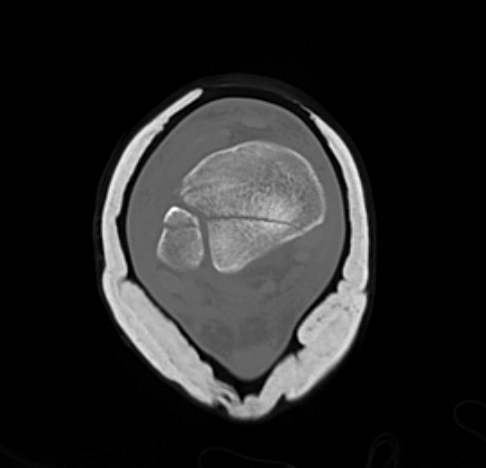

Posterior Malleolar Fractures

- occult in 70%

- especially with spiral distal tibial fractures